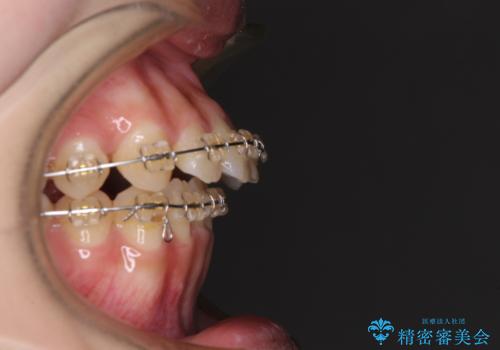

- 大学病院にて装置を装着したものの、治療が十分に受けることができないとのことで転院をされた患者様です。

上顎歯列が前方にあり、口元が閉じにくくなっていたため、既に装着されている装置を使用して上顎歯列全体を後方に移動させていくこととしました。

舌の突出癖があり、それが原因で上下前歯に隙間ができていたため、改善のためのトレーニングを行うように指示をしました。

舌の突出癖の影響か、なかなかスペースが閉じきらず、治療期間は予定よりも長期間となりました。

舌突出癖改善のトレーニングの重要性を認識することとなりました。